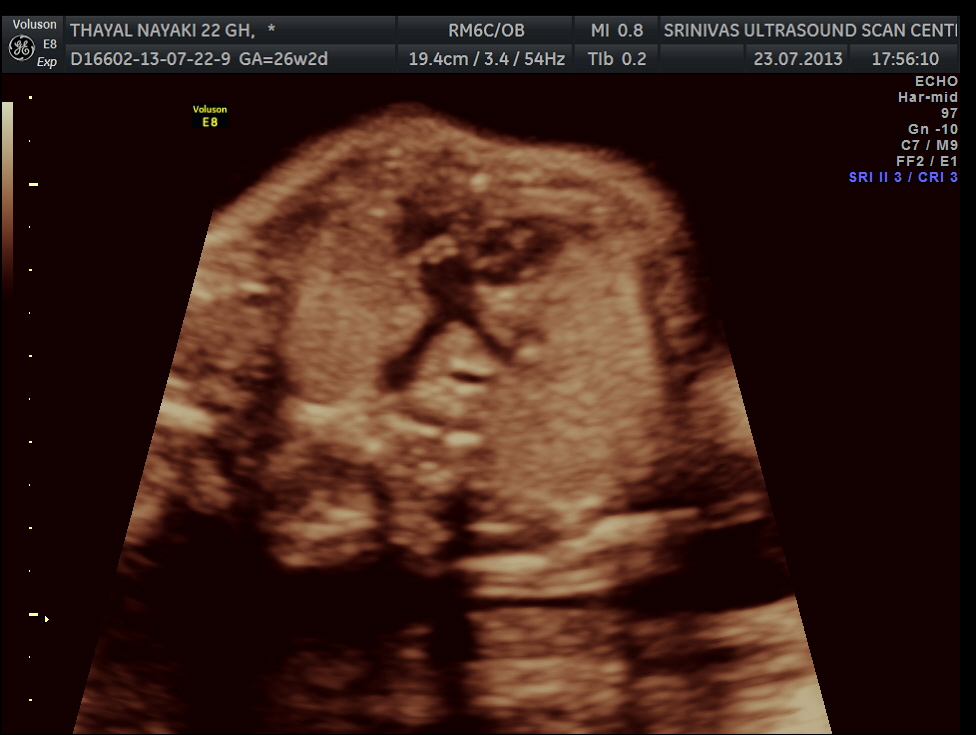

The cardiac axis appeared to be abnormal .

4 chamber view is given below .

3 vessel view shows a prominent single vessel , which is very suggestive of outflow tract anomalies like transposition of great arteries, double outlet right ventricle , truncus arteriosus and corrected transposition of great arteries.

another view of the above two